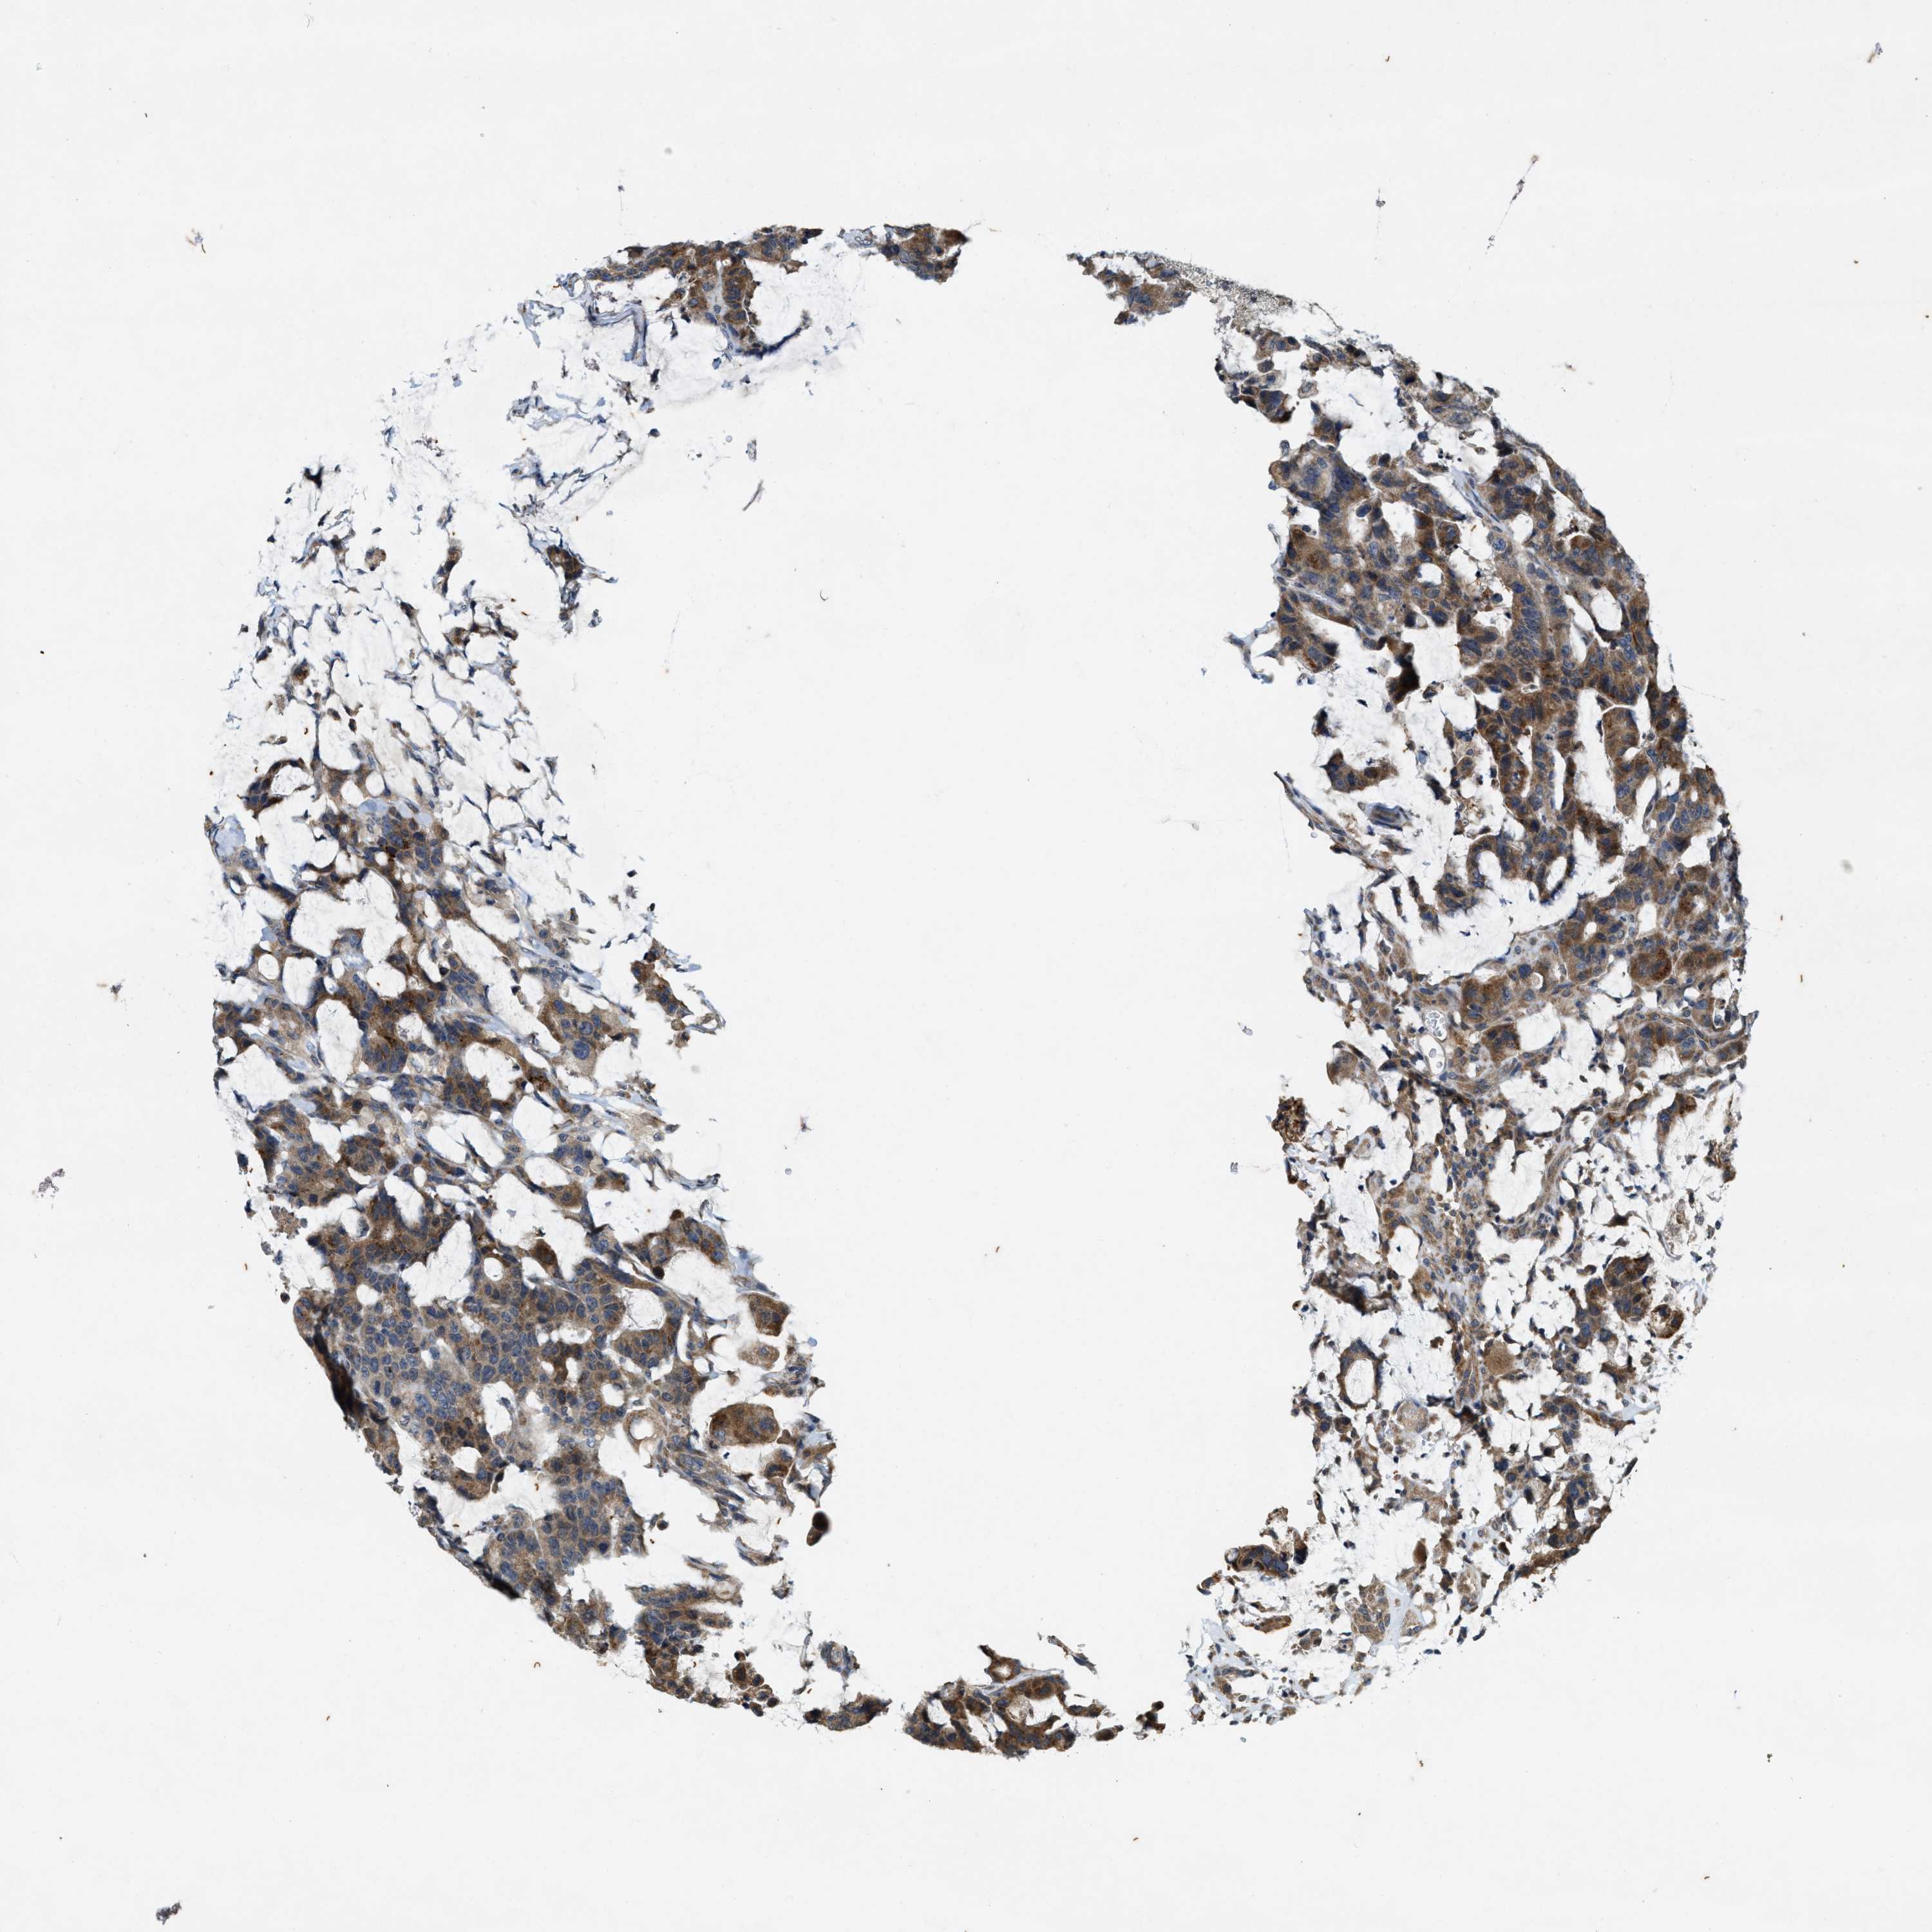

CANCER COLORECTAL CANCER Show tissue menu

Colorectal cancer

Human cancer

Colon adenocarcinoma